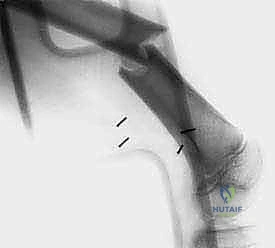

- الأشعة السينية (X-ray): الخطوة الأولى لتقييم العظام وتحديد نمط التدمير العظمي.

* الكسور المرضية: حدوث كسر في العظم نتيجة إصابة طفيفة جداً لا تسبب كسراً في العظم السليم، مما يدل على ضعف العظم بسبب ورم.

الحالة الأولى: إنقاذ ركبة رياضي شاب

شاب يبلغ من العمر 19 عاماً عانى من ألم مستمر في الركبة وتورم لم يستجب للمسكنات. بعد الفحص السريري الدقيق وإجراء الرنين المغناطيسي، اشتبه الأستاذ الدكتور محمد هطيف بوجود ورم. تم إجراء خزعة إبرة أساسية دقيقة جداً. أظهرت النتائج وجود "ساركوما عظمية" في مراحلها الأولى. بفضل الخزعة الدقيقة التي لم تلوث الأنسجة المحيطة، تمكن الدكتور هطيف لاحقاً من استئصال الورم بالكامل وتركيب مفصل صناعي خاص بالأورام، مما أنقذ ساق الشاب من البتر ومكنه من العودة للمشي بشكل طبيعي.